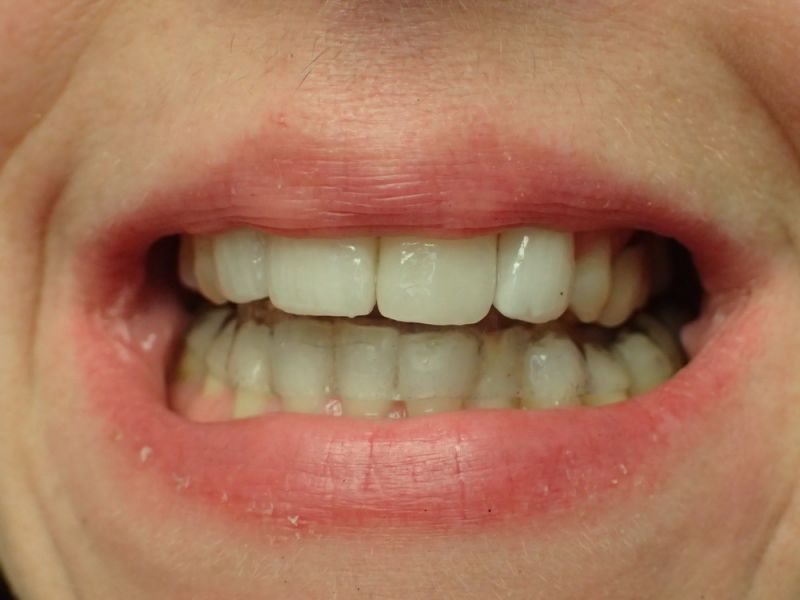

Patientin von der dänischen Grenze erhält einen adjustierten Aufbissbehelf

Obwohl die Patientin erkennbar eine gute Mundhygiene beteibt, zeigt sich im gesamten Oberkiefer und hier vor allem im Bereich der Backenzähne ein ausgeprägte und altersuntypisch weit voran geschrittener Knochenabbau.